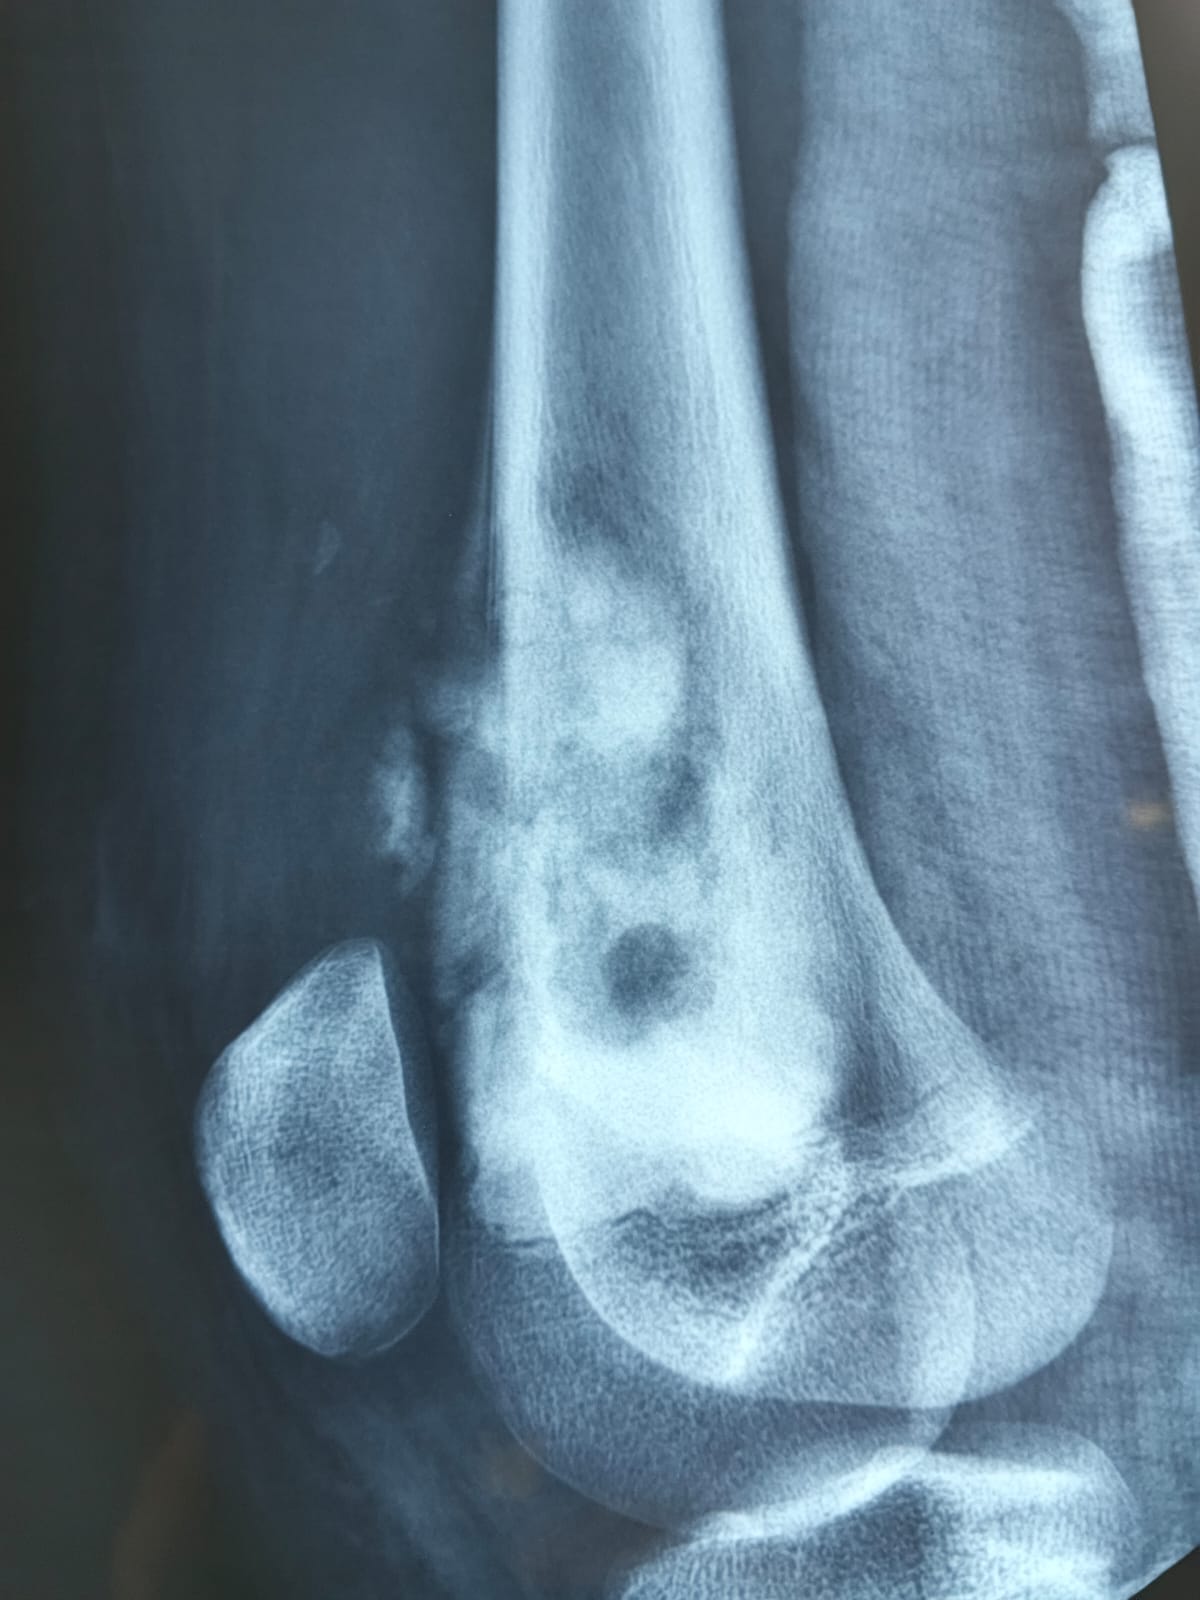

La hematología pediátrica se enfoca en el estudio y tratamiento de enfermedades de la sangre en niños. En Angelito Guardián, abordamos condiciones hematológicas con tecnología avanzada y un enfoque humano.

Contamos con procedimientos de alta complejidad para lograr un diagnóstico certero: